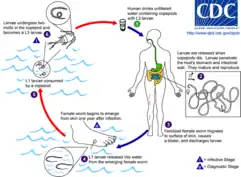

Life cycle

D. medinensis L1 larvae are found in fresh water, where they are ingested by copepods (small crustaceans) of the genus Cyclops. Within the copepod, the D. medinensis larvae develop to an infective L3 stage within 14 days.[9] When the infected copepod is ingested by a mammalian host drinking unfiltered water, the copepod is then dissolved by stomach acid and dies and the D. medinensis larvae are released and migrate through the wall of the mammalian intestine, and enter the abdominal cavity and retro-peritoneal space, where they mature into adults. After maturing and mating within the host, the males die and females (length 70–120 cm) migrate in subcutaneous tissue towards the skin's surface. Around a year after the infection, the female causes the formation of a blister on the skin's surface, generally on the lower extremities, though occasionally on the hand or scrotum. When the blister ruptures, the female slowly emerges over the course of several days or weeks.[9] This causes extreme pain and irritation to the host. During those few days to hours before the worm exits the skin, the person may develop a fever, pain, or swelling in that area. When the host — in an attempt to alleviate the excruciating burning pain — submerges the affected body part in water, the female releases thousands of larvae into the water. From here, the larvae infect copepods, continuing the life cycle.[9] After the worm exits the skin the wound caused by the emerging worm often develops a secondary bacterial infection. Permanent damage can occur if the infection goes untreated around a joint. Most cases occur in areas without access to health care facilities.[10]